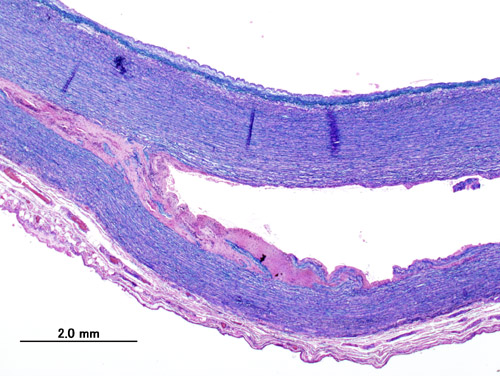

내막 파열의 원인은 항상 명확하지는 않지만, 종종 중막을 구성하는 콜라겐과 엘라스틴의 변성을 포함한다. 이를 낭성 중막 괴사라고 하며, 마르판 증후군과 가장 흔하게 관련이 있으며 엘러스-단로스 증후군과도 관련이 있다.[24][25]

대동맥 박리의 약 13%에서는 내막 파열의 증거가 발견되지 않는다. 이러한 경우, 유발 사건은 중막 내 출혈에 의한 혈종으로 생각된다. 이 경우 진성 내강과 가성 내강 사이에 직접적인 연결이 없으므로, 대동맥 조영술로 대동맥 박리를 진단하기 어렵다(원인이 중막 혈종인 경우). 중막 혈종에 의한 대동맥 박리는 내막 파열에 의한 것과 동일하게 치료해야 한다.[24][25]